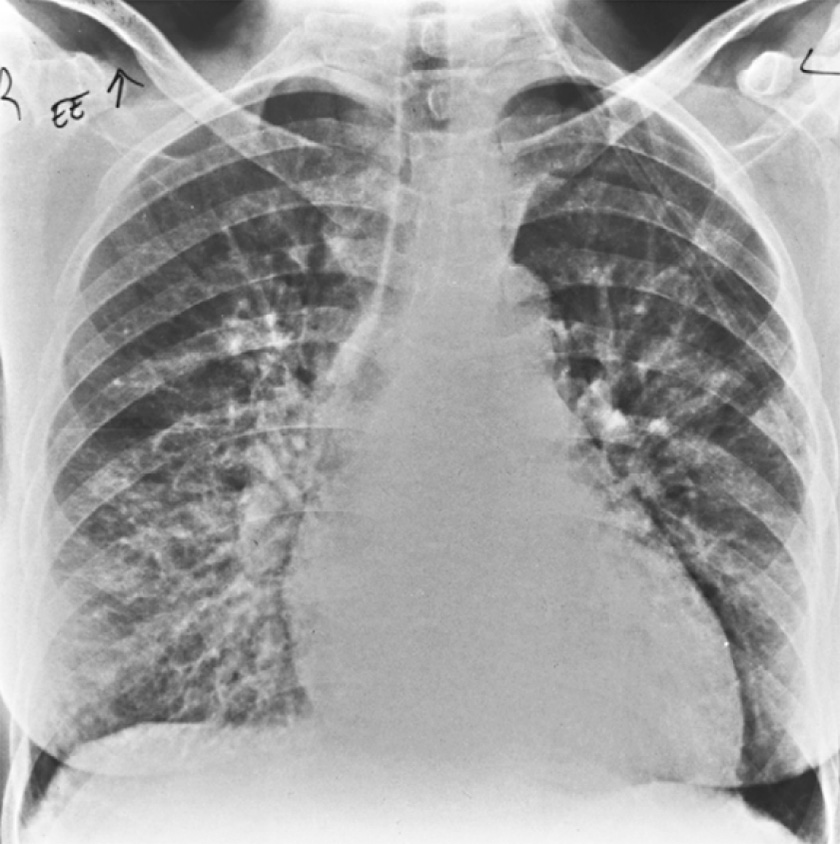

Волчаночный пневмонит (люпус-пневмонит) характеризуется одно- или двусторонними участками интерстициальной инфильтрации по типу «матового стекла», которые могут сочетаться с альвеолярной инфильтрацией. Эта патология встречается гораздо реже. Отметим, что при системной красной волчанке может возникать легочное кровотечение, при этом на рентгенограмме легких определяются распространенные инфильтраты (рисунок 1). Кроме этого, при системной красной волчанке в нижних отделах легких могут обнаруживаться фиброзные изменения, однако выраженный фиброз и «сотовое легкое» развиваются редко.

Рисунок 1. Поражение легких при системной красной волчанке. На рентгенограмме, выполненной у больного с кровохарканьем, обусловленного обширным легочным кровотечением, в прикорневой зоне и среднем легочном поле справа определяется высокоинтенсивная, нечетко ограниченная инфильтрация, также в нижней доле слева визуализируется начальная инфильтрация. Слева отмечается небольшой плевральный выпот

Рисунок 4. Острый пневмонит при системной красной волчанке. В нижнем и среднем отделе правого легкого определяется усиление рисунка с образованием ретикулярных теней и неоднородной инфильтрации. Гистологическое исследование биоптата показало васкулит и кровоизлияние